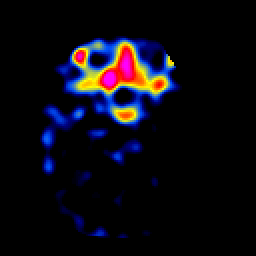

SPECT TL Study #2 -- Slice #17

[Home][Help][Clinical][Tour 1][Tour 2][Tour 3] Slice 17